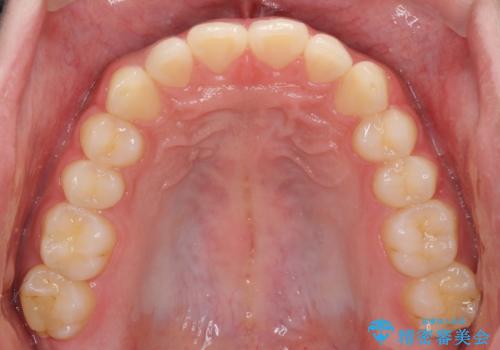

インビザラインによる、すきっ歯の改善

- 前歯がすきっ歯であることを気にして来院された患者様です。

下の前歯がほとんど隠れてしまうくらいの深い咬み合わせであったので、インビザラインを用いて、咬み合わせの高さを改善しながら隙間を閉じていくこととしました。

咬合力で上の前歯が前方に押し出されるようにして隙間ができていましたが、矯正治療により全て閉じることができました。

深い咬み合わせも多少改善され、隙間も閉じたことで、前方に出ていた前歯が引っ込んだため、口も閉じやすくなったとのことでした。